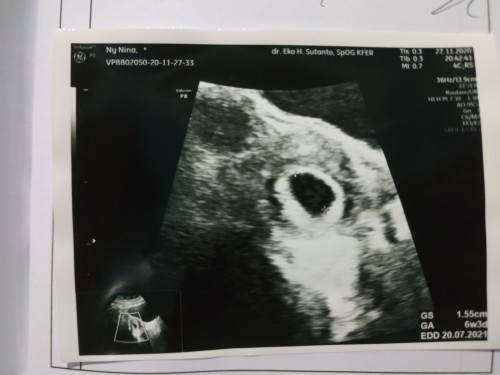

Ada yg pernah ngalamin gak bun pas tahu positif hamil bunda langsung cek ke bidan dan kata bidan sesuai hitungan hpht usia kandungan udah masuk 8/9w dan gak ada rasa mual/pusing, makan pun lancar. Tapi pas cek ke dokter hasil usg nunjukin usia kandungan baru menginjak usia 6/7w masih berbentuk kantok janin bun dan suka banget sakit perut bagian bawah kaya mau datang bulan itu kira2 janin nya tidak berkembang atau bagaimana ya bun jadi hawatir 🙈#seriusnanya #jangandibully #firstbaby